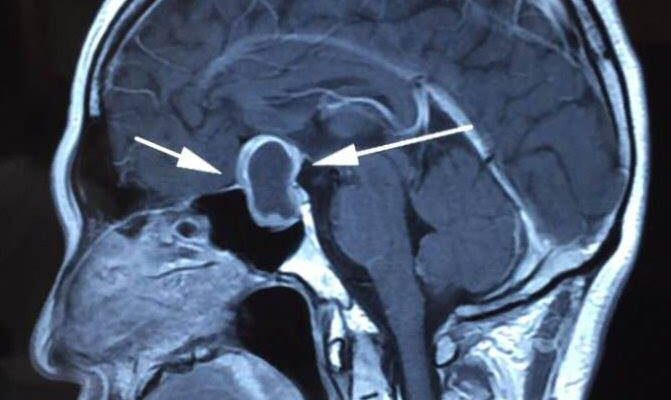

任何懷疑有腦下垂體腺瘤的患者必須接受至少二個測試,一是以磁力共振掃描(MRI)檢查腦部碟鞍位置。這個測試提供解剖資訊確定腺瘤是否有侵犯鄰近結構或出現視交叉的壓迫,比如海綿體靜脈竇;第二個測試是一個充分的內分泌血液評估,用以確定腫瘤是否影響激素水平。如果腫瘤較大,還需要一個視力評估及視野檢查,這個測試可幫助診斷腫瘤是否影響了視覺神經。